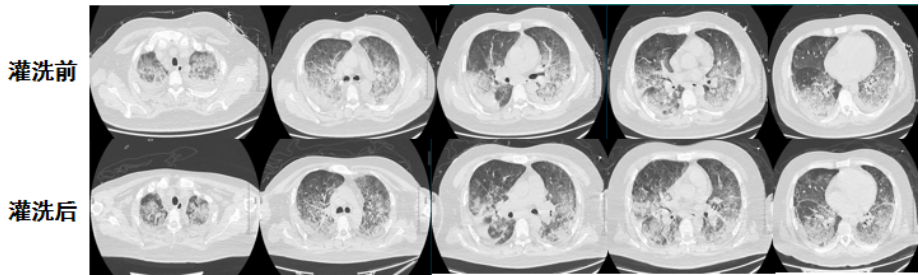

治疗措施:维持治疗,行全肺灌洗+抗感染治疗;积极推进骨髓移植。灌洗后患者影像学表现显著改善(图7)

图片

图7  全肺灌洗前后患者影像学变化